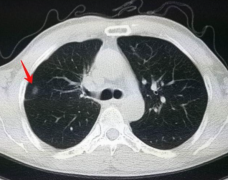

肺作为人体最重要的呼吸器官,是维持人体正常功能的必要保障。然而近些年来,越来越多的人肺部出现问题,不仅肺癌变得越来越高发,而且随着螺旋CT等检查手段的应用,很多人也